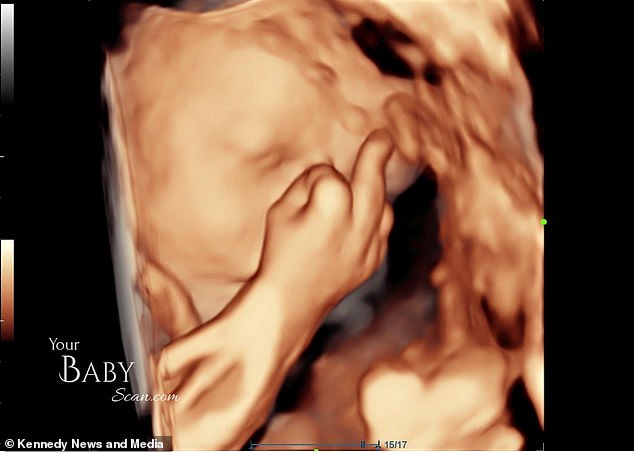

Родители были потрясены, когда их сын показал средний палец. На веселых фотографиях 4D-сканирования видно, как маленький мальчик закрывает лицо, зевает, а затем показывает неприличный жест.

«За пять минут до конца он решил показать нам средний палец, как бы говоря: хватит, мама и папа, оставьте меня в покое», – сказала девушка.